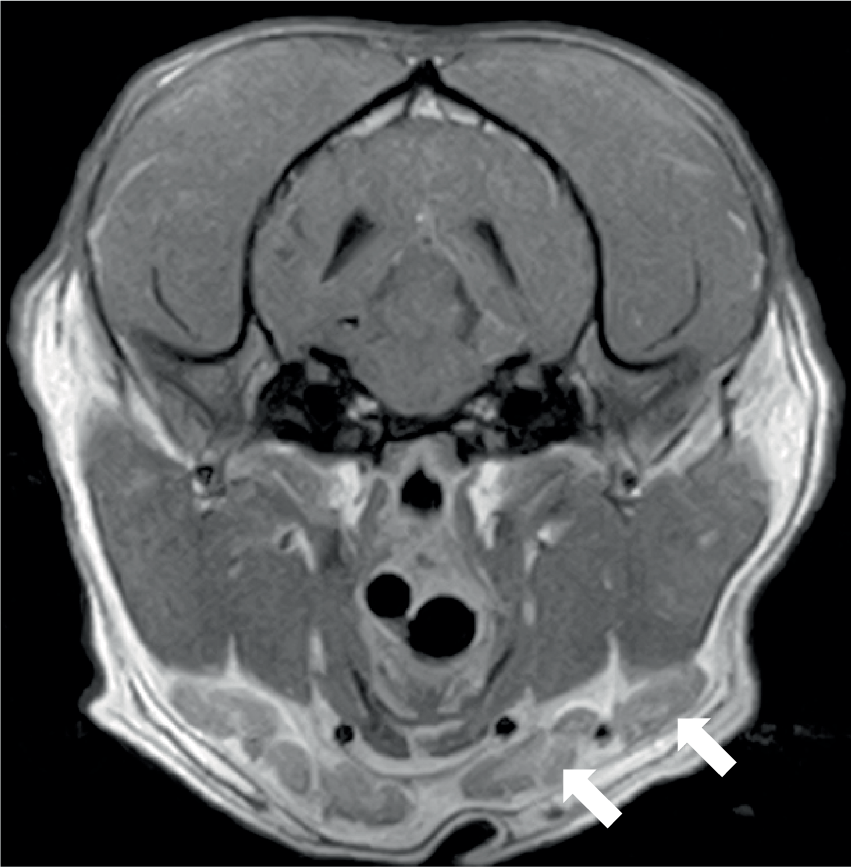

Three dogs showed bone marrow remodeling on MRI. This was characterized by heterogeneous loss of fat opacity of normal bone marrow on T1 and a lack of suppression on STIR (Figure 4), and one dog showed mildly increased contrast enhancement of the bone marrow. These changes were noted in bones adjacent to abnormal musculature or meninges, as described above (calvarial bone n = 2; manubrium and scapulae n = 1). All dogs had mild to moderate lymphadenopathy (Figure 5) of various lymph nodes within the field of view (FOV) (Figure 5).

Figure 4

Transverse T1W image of the brain of a 6-year-old English Springer Spaniel showing a reduction in the normal hyperintense signal from calvarial bone marrow (arrowed). The same dog, as shown in Figures 1A,B.

Figure 5

Transverse post-contrast T1W image of the head of a 2-year-old English Bulldog showing enlarged mandibular lymph nodes (arrowed). The same dog is shown in Figure 1C.